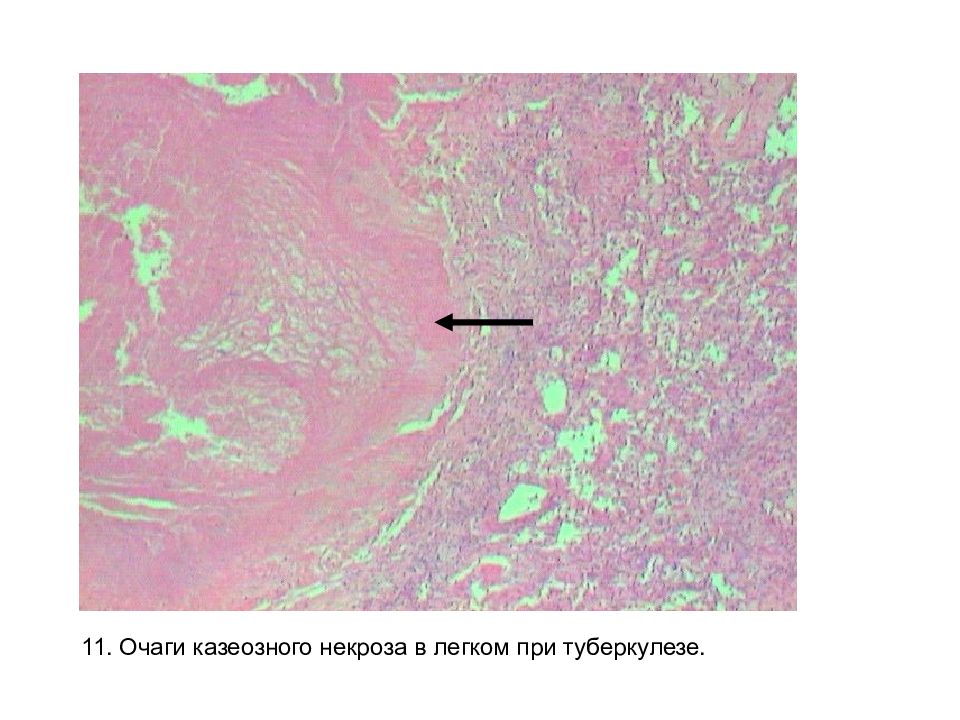

Карнификация Легкого: Микропрепараты и Диагностика

Раздел: Калейдоскоп образов